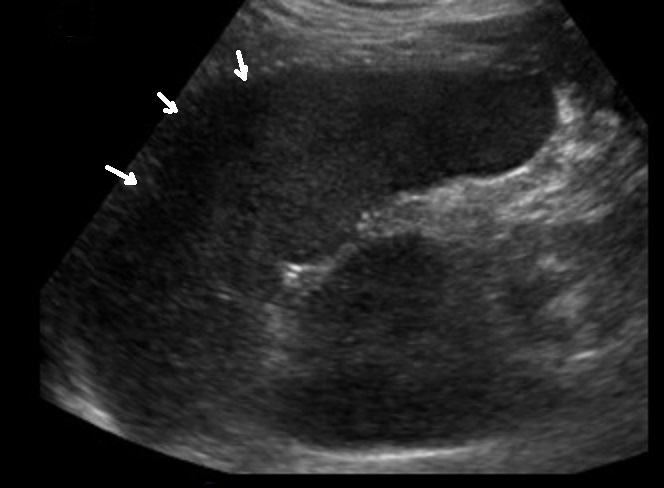

Dans les traumatismes de la

rate de grade grave de II - V , la signe indirecte

de traumatisme le plus souvent s'observe est image

de hemoperitoine peri-splenique ou globale

intra-peritoneale . Au dessus c'est image de

hemoperitoineale locale peripherique externe de la

rate , c'est une zone de hypoechogene a bien limite

peri-splenique . |

Image

echographique d'une traumatisme de la rate

compliquee avec une hemoperitoine localise

peripherique de la rate . On peut en s'observe de

zone hypoechogenecite a bien limite a inferieure et

a peri-splenique |